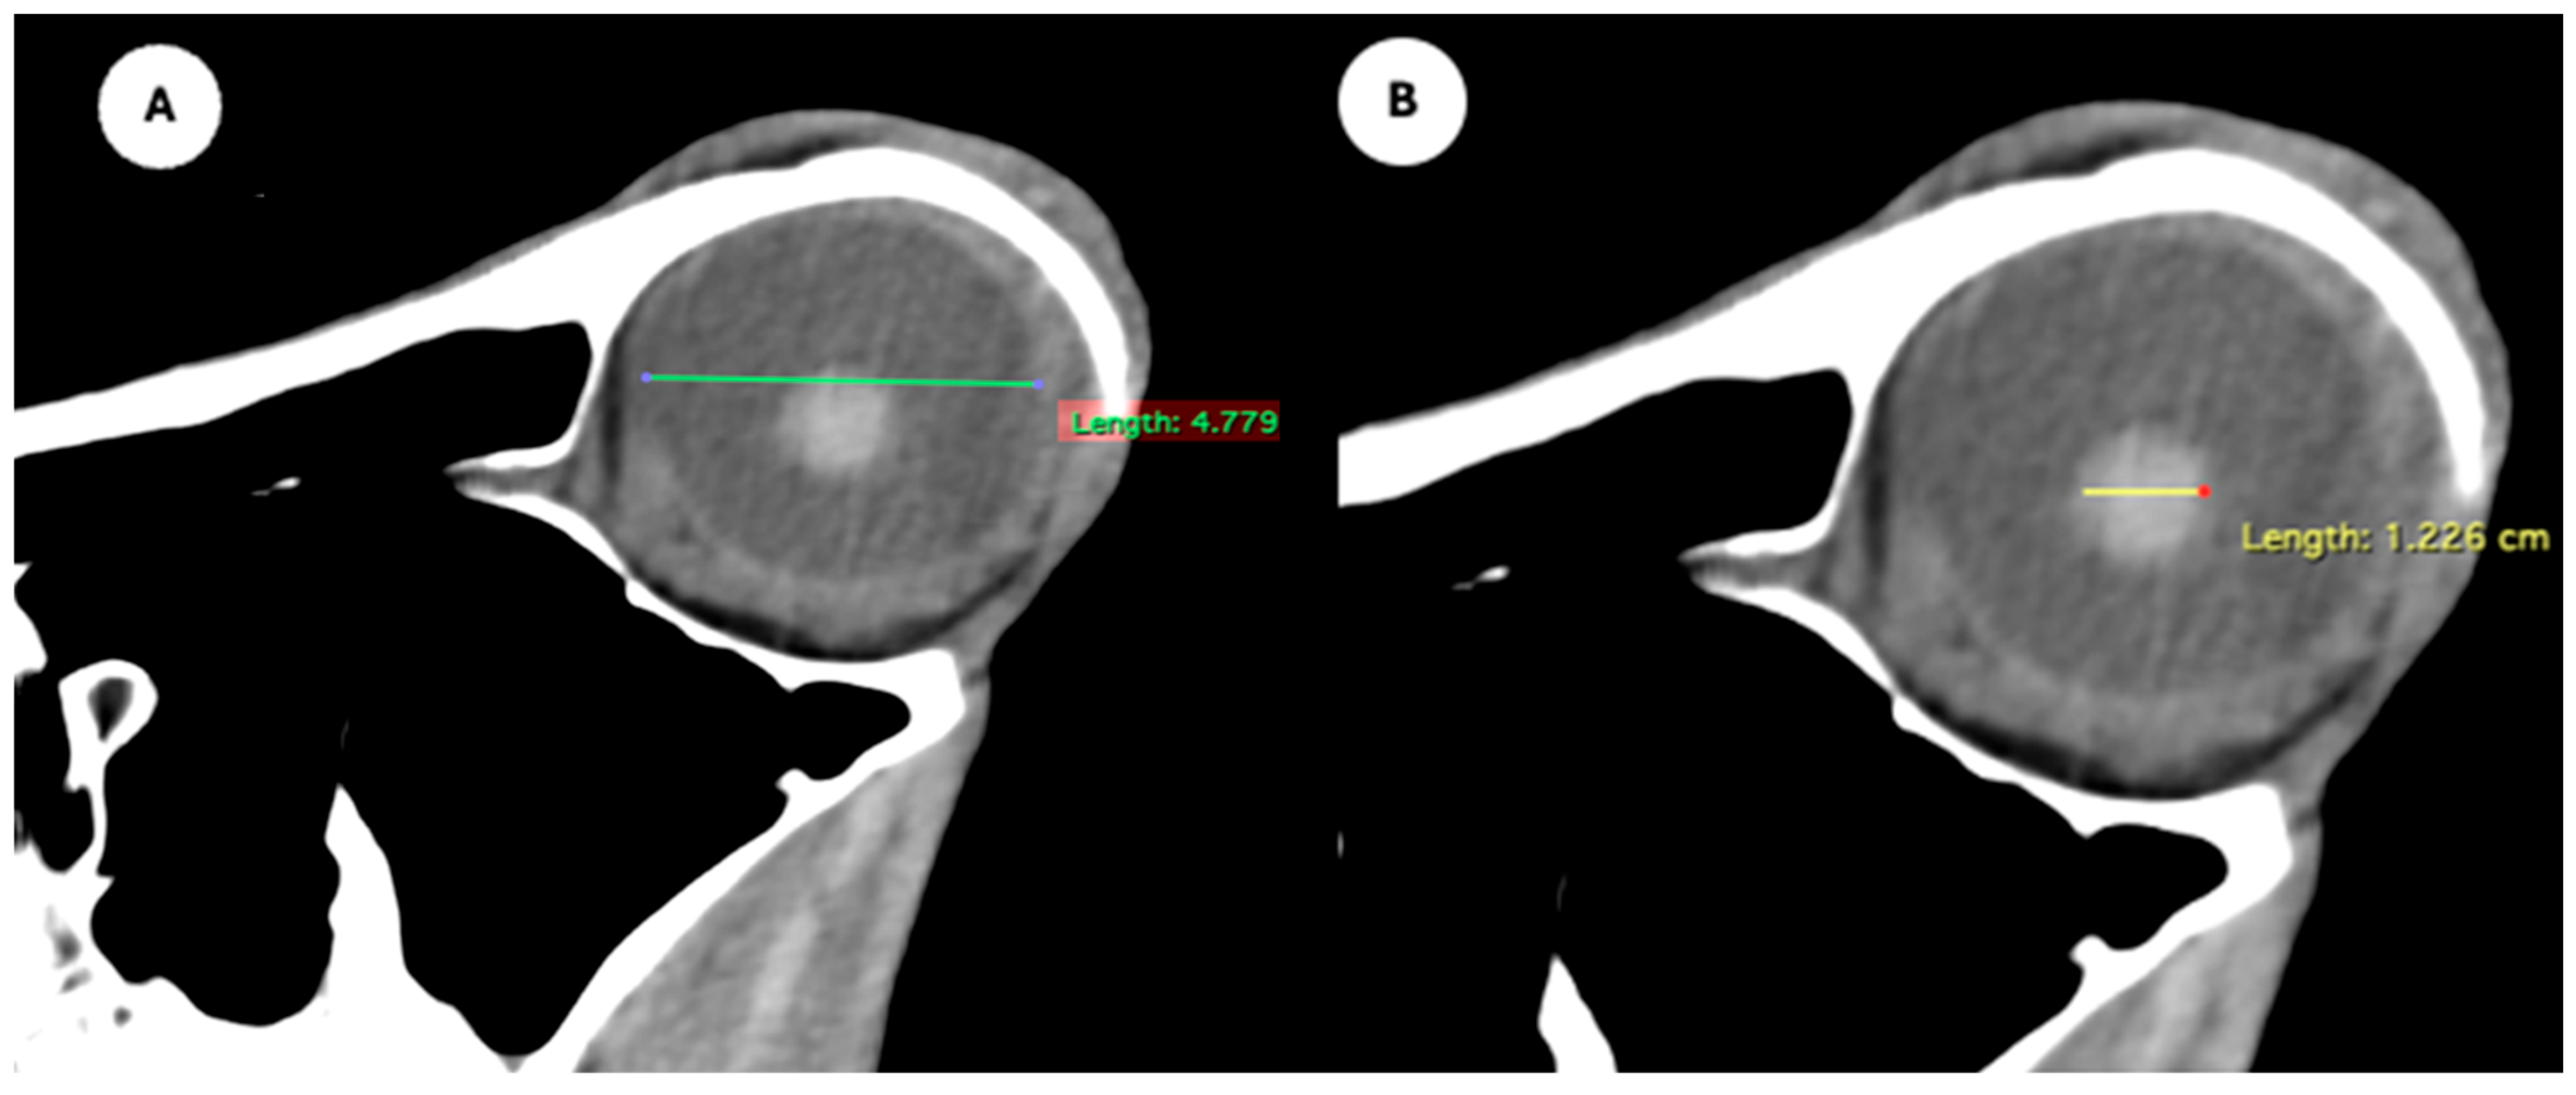

Figure 1. (A) Transverse multiplanar reconstruction (MPR) of the equine eyeball showing the maximum anterior–posterior distance (axial length), measured from the external surface of the cornea to the internal surface of choroid/retina/sclera, and the maximum latero-medial distance (equatorial width), measured perpendicular to the axial length. (B) Transverse MPR illustrating lens dimensions, with the latero-medial distance (equatorial width), measured at its widest point.

- Eyeball equatorial width and height: Maximal anterior–posterior distance (Figure 1A) and maximal lateromedial distance of the eyeball, measured perpendicular to the axial length (Figure 2B).

Table 1 provides summary statistics (mean, median, range, and standard deviation) for the internal ocular measurements of the left eye, right eye, and both eyes combined across all 20 horses. The average ocular measurements indicated that the eyeball height (5.19 ± 0.13 cm) was greater than its width (4.28 ± 0.12 cm), confirming the characteristic oval shape of the equine eye. The mean axial length was 5.09 ± 0.17 cm, consistent with previous descriptions of large-globe morphology in horses. The orbital cavity measured 5.27 ± 0.12 cm in height and 6.29 ± 0.14 cm in length. The anterior and posterior chambers had mean widths of 0.56 ± 0.07 cm and 2.26 ± 0.09 cm, respectively. The lens exhibited a mean height of 1.53 ± 0.06 cm, width of 1.23 ± 0.06 cm, and length of 1.63 ± 0.04 cm. These results collectively reflect the regular proportions and bilateral symmetry of the equine eyeball and its internal structures, as detailed in Table 1. The Mann–Whitney U test revealed no statistically significant differences in the measurements between the right and left eyes. Similarly, when all variables were considered collectively, the analysis confirmed the absence of significant differences between both eyes